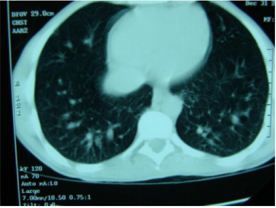

CT scan of the chest showed bilateral dilatation of the peripheral pulmonary vasculature (Figure 1). Transthoracic ECHO was normal. Transoesophageal echo with agitated saline showed the appearance of the air bubbles in the left atrium after 8 cardiac cycles due to the presence of intrapulmonary dilatation and shunting (Figure 2). This triad of chronic liver disease, intrapulmonary arteriovenous shunts causing shortness of breath, and hypoxia constitutes the Hepatopulmonary Syndrome (HPS). The patient was discharged on long term home oxygen therapy, with improvement in his symptoms. Family were advised to go for liver transplant.

The chest radiograph is frequently non-specific. Arterial blood gas analysis shows type 1 respiratory failure with alkalosis. Pulmonary function tests show normal spirometry and lung volumes. Carbon monoxide diffusion capacity is low, arterial and alveolar oxygen gradient is high. CT lungs with contrast shows dilatation of peripheral pulmonary vessels with normal central pulmonary vessels. Contrast-enhanced Transoesophageal echocardiography has been a valuable tool for showing the presence of intrapulmonary vascular dilatations in patients with HPS. First, it will rule out the presence of intracardiac shunts and confirm the presence of pulmonary shunts as the microbubbles are delayed till after the third cardiac cycle as they pass through the pulmonary shunts and bypass the alveoli. Other methods include lung perfusion scan, pulmonary angio, technichium-99m-labelled macroagregated albumin.